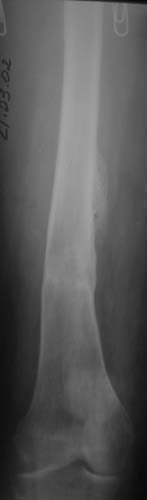

Наше общее мнение - проведение клиновидной остеотомии в зоне дополнительной точки опоры с ее иссечение и укорочением бедра, протезирование ножкой Вагнера.

Похожий случай представляем на ретгенограммах. Операция выполнена в 1996 г.